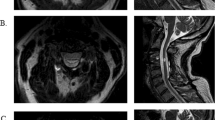

The absolute average CSA of muscle stimulated in the AB controls was significantly greater than in the SCI patients [44 (6) cm2 versus 16 (3) cm2, P<0.05], due to the atrophied mQF of SCI subjects. However, in a relative sense, there was a higher proportion of the mQF stimulated in the SCI group [90 (2) versus 66 (4)%, P<0.05; Fig. 2]. Despite the small mQF of SCI patients and the long duration since injury, the available motor units responded quite well to stimulation. Overall, EMS torque was predicted by the following equation: torque (Nm) = 3.74 × stimulated CSA (cm2) − 14.37 (R 2 = 0.93, P<0.05, Fig. 3). The relative mQF CSA with an elevated T2 on day 3 was significantly higher for SCI than AB subjects (25% versus 2% of activated muscle, P<0.05, Fig. 4). The damaged area was normalized to the amount of muscle activated on day 1. AB subjects showed no decline in MVC 3–4 days post stimulation (plus/minus 5%), yet SCI subjects’ electrically stimulated torque was reduced by 22%.

Representative single slice, binary T2 map of the quadriceps femoris muscle (mQF) for one able-bodied (upper row) and SCI (lower row) subject pre (left), immediately post (middle), and 3 days post (right) EMS, respectively. Black represents muscle at rest, borders drawn for clarity. In general, SCI subjects had smaller mQF cross-sectional area (CSA) but larger relative amount of muscle stimulated and injured